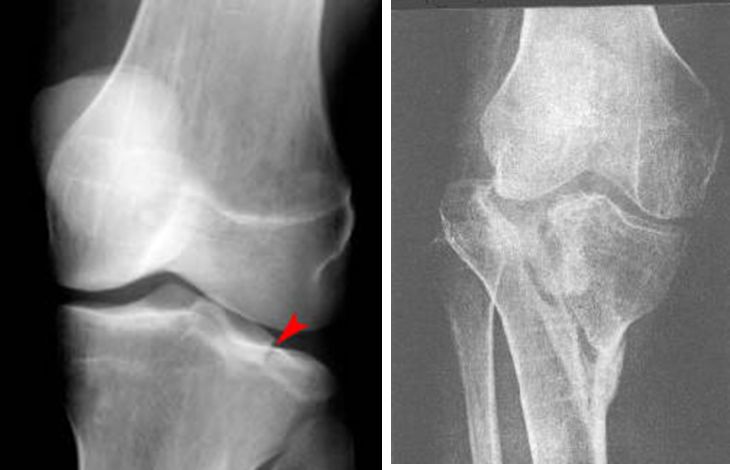

胫骨平台骨折